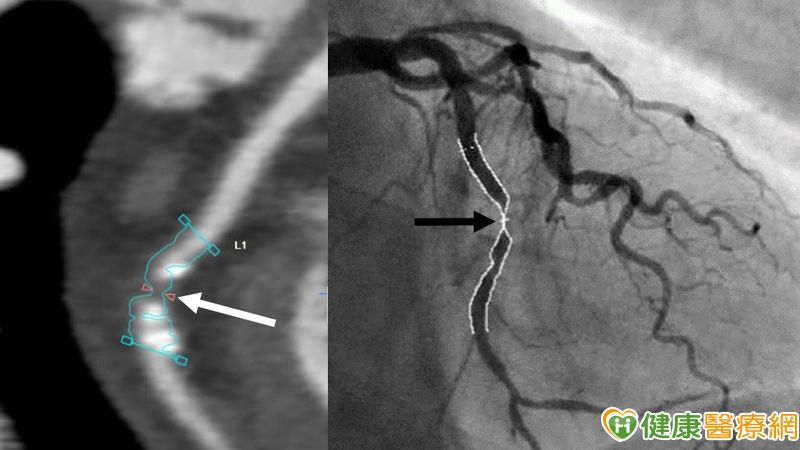

▲一60歲男性患者,近兩個月胸痛不適、心電圖異常,做冠狀動脈電腦斷層血管攝影 (CCTA) 呈現左迴旋支動脈有鈣化和嚴重狹窄 (狹窄直徑 > 70%) (白箭號),經心導管檢查證實(黑箭號)和置放支架治療後,成功避免發生心肌梗塞